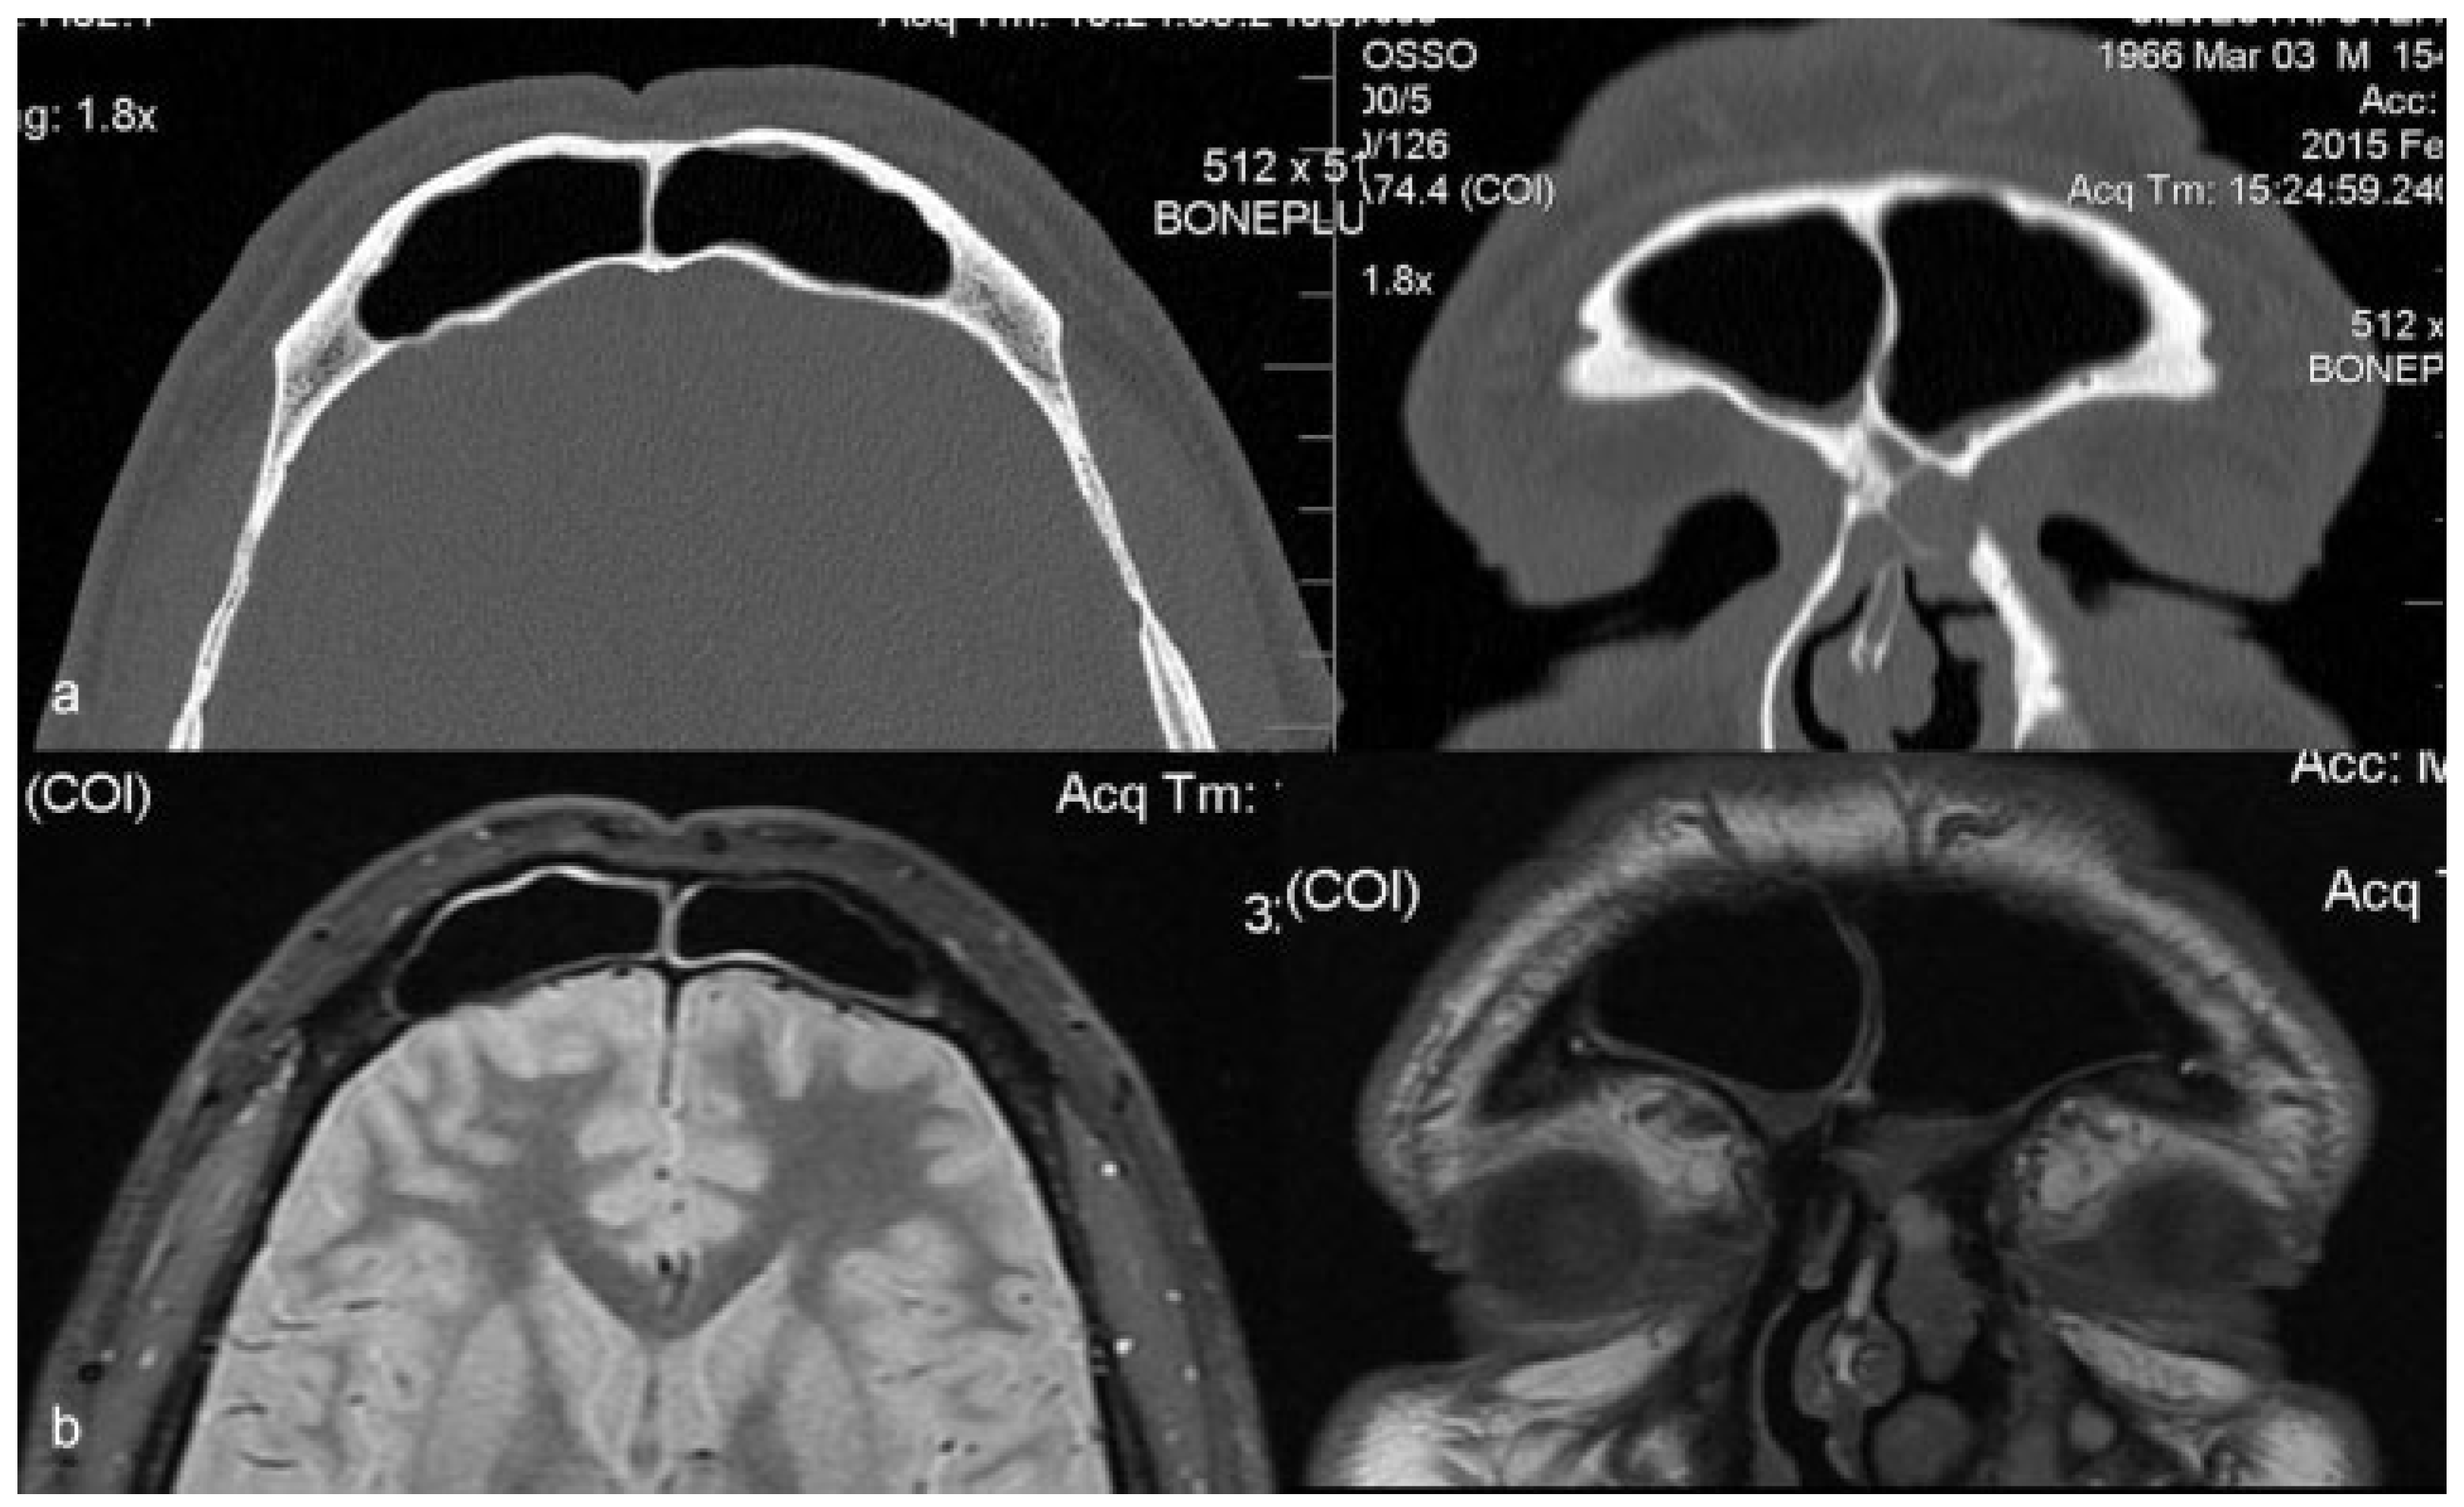

Computed tomography (CT) revealed a wide loss of substance in the root of the nose and a cystic neoformation involving the nasal bones (Figure 2). Magnetic resonance imaging (MRI) showed a globular cystic lesion with a fluid content occupying the upper region of the root of the nose and partially protruding into the nasal cavity (Figure 3). CT scan and MRI showed no involvement of the frontal sinus and frontal recess (Figure 4).

Figure 4. Preoperative CT scan (a) and MRI (b): no frontal sinus and frontal recess involvement.